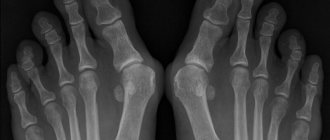

Сведение пальцев ног

Судороги пальцев ног появляются из-за нарушения местного кровотока в мелких капиллярах и артериях. Иногда причиной патологии является аномалии развития связочного аппарата. К основным причинам относят:

• плоскостопие любой степени выраженности;

• травмы пальцев (ушиб, падение тяжелого предмета, растяжение или переломы).

Пальцы на ногах стопы, как и сама подошва, имеют множество капилляров и нервных ответвлений. При ущемлении нервных корешков возможно онемение пальцев с сильными болями и судорогами.